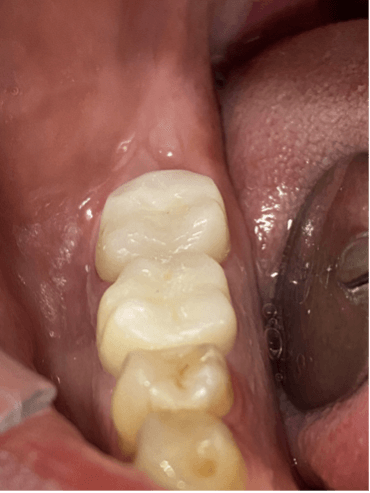

Kanala kalsin yerleştirildi (RESİM12). 4. seansta hastamızda herhangi bir semptom yoktu, distal kanal biodentin mesial kanallar guta ve Ahplus ile dolduruldu (RESİM13). Kanal tedavisi tamamlandıktan sonra dişin koronal restosrasyonu zırkonya kaplama ile gerçekleştirildi ve hastamız takibe alındı. (RESİM14)

Final görsel (RESİM 15)

RESİM 14: Kanal tedavisi sonrası zırkonya restorasyonlar

RESİM 15 : Final Görsel